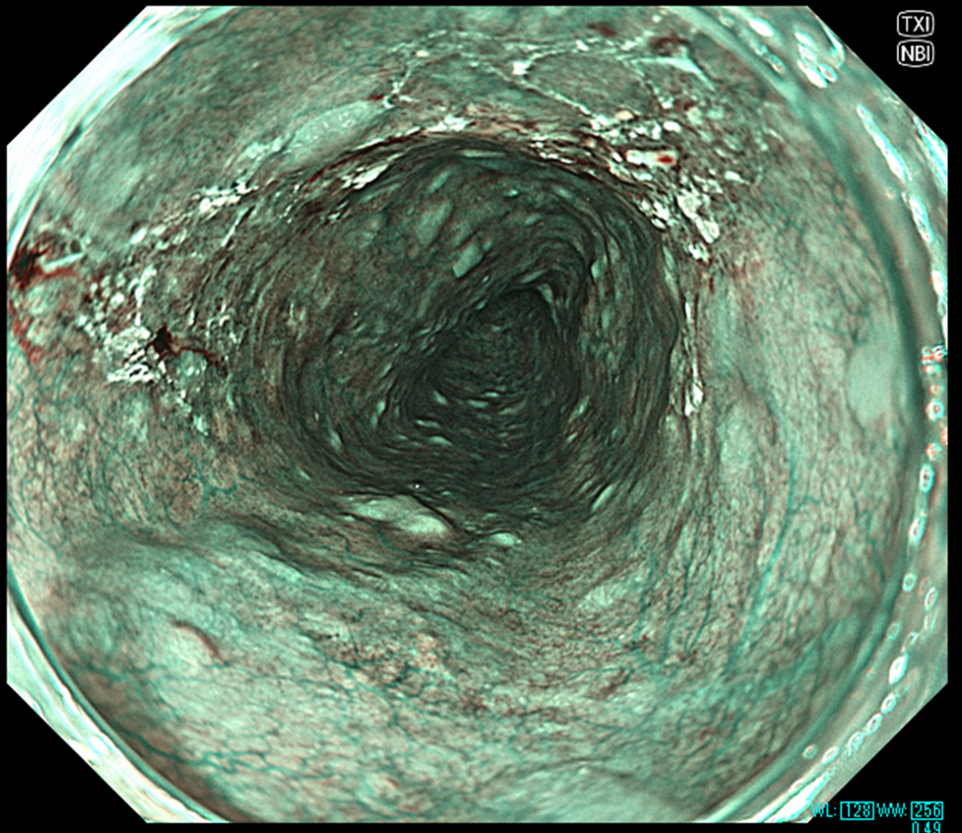

食道表在癌のNBI画像(左)およびNBI+TXI画像(右)の比較

NBI+TXIでは明度の上昇や輪郭の強調により腫瘍の存在が強調される。